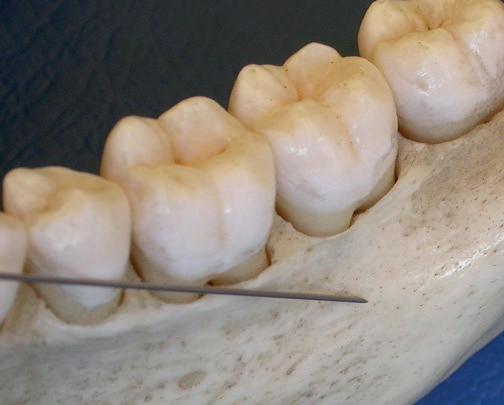

Om een subgingivale reiniging zo goed mogelijk te kunnen uitvoeren en tot een mooi behandelresultaat te komen, zijn kennis over instrumentarium en kennis over de morfologie van het element (kroon, radices, furcaties en de omliggende weefsels) erg belangrijk. Daarnaast is het essentieel om de verschillende technieken om subgingivaal te reinigen goed onder de knie te hebben. Wat kun je bereiken met subgingivaal reinigen en welke beperkingen kunnen een goed eindresultaat beïnvloeden? Tijdens deze cursus zullen we zowel reiniging met ultrasone apparatuur als reiniging met handinstrumenten bespreken en zullen we onder begeleiding oefenen met deze behandelmethodes.

De cursus bestaat uit een theoretisch en een praktisch deel. Tijdens het praktische deel van de cursus, zal worden geoefend op een fantoomhoofd om te oefenen met de verschillende technieken, zodat die daarna in de praktijk weer direct toepasbaar zijn.

Leerdoelen

De cursist:

• Verkrijgt inzicht in de anatomie van de radices

• Verkrijgt inzicht in de mogelijkheden en beperkingen van subgingivale reiniging

• Kan bepalen welke techniek van verschillende soorten een patiënt

• Is bekend met de contra-indicaties voor toepassing van ultrasone apparatuur

• Verkrijgt kennis van verschillende soorten instrumentarium en de toepassingsmogelijkheden

• Verkrijgt kennis van de verschillende type tips en de toepassingsmogelijkheden

• Kent het verschil in behandelresultaat tussen handmatig vs. ultrasone reiniging